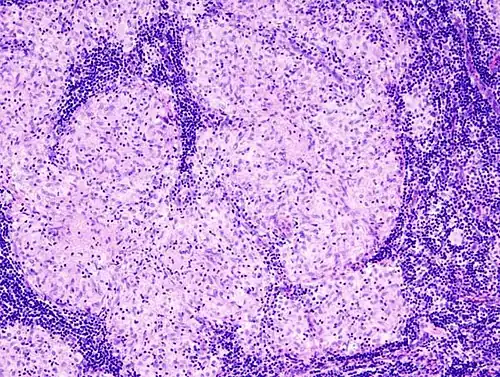

Histopathology

Sarcoidosis is characterized by the formation of non-necrotizing ("non-caseating") granulomas in various organs and tissues.[95] Giant cells, specifically Langhans giant cells, are often seen in sarcoidosis.[96] Schaumann bodies seen in sarcoidosis are calcium and protein inclusions inside of giant cells as part of a granuloma.[97] Asteroid bodies can be seen in sarcoidosis.[97] Hamazaki–Wesenberg bodies can be seen in lymph nodes and more rarely in lung biopsies with sarcoidosis and are inclusion bodies of lysosomes with protein, glycoprotein and iron.[98]

-

Sarcoidosis in a lymph node -

Schaumann body in sarcoidosis -

Asteroid body in sarcoidosis -

Hamazaki–Wesenberg bodies in sarcoidosis in lymph node